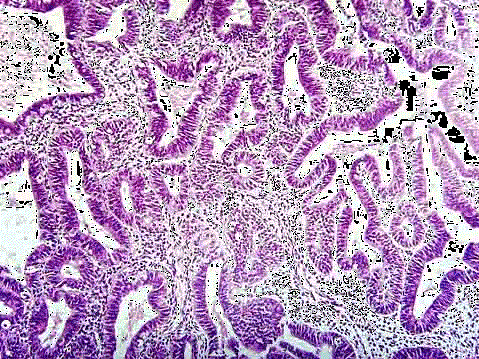

问题 女性,40岁,月经量多不规律2月余,诊刮子宫内膜,显微镜下见腺体增生,与间质比>3:1,腺上皮部分出现假复层,核无明显异型(如图),应诊断为 ( )

选项 A.子宫内膜单纯性增生 B.子宫内膜复杂性增生 C.子宫内膜单纯性增生伴非典型增生 D.子宫内膜复杂性增生伴非典型增生 E.子宫内膜腺癌

答案 B